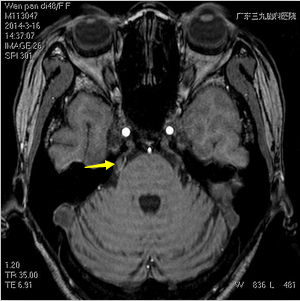

术前图片

结合患者的病史及检查,医生诊断为:1、三叉神经痛;2、风湿性心脏病(二尖瓣球囊扩张术后 心房纤颤 二尖瓣轻度狭窄病轻度反流主动脉瓣关闭不全);3、脑梗塞恢复期;4、颈椎病(颈型)。

经过科室讨论,医生考虑患者的三叉神经痛可行手术治疗,虽然身体状况差,但非绝对手术禁忌。几日后,温女士在全麻下接受了右侧三叉神经微血管减压术,术后患者精神、饮食、睡眠好,头痛、面部疼痛的问题未再出现。